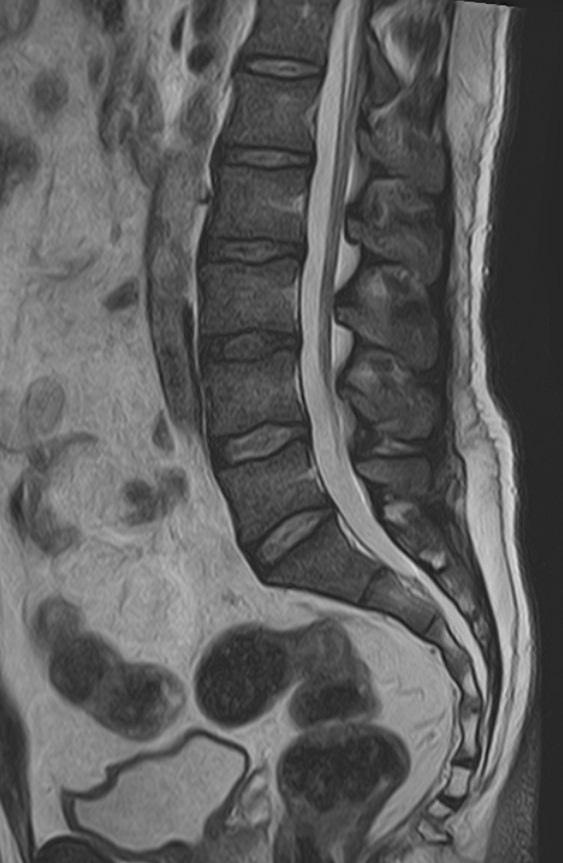

К центральной нервной системе организма относится головной мозг, расположенный в полости черепа, и спинной мозг, проходящий в спинномозговом канале позвоночного столба. В головном мозге находятся высшие центры управления всем организмом, спинной мозг имеет двусторонние связи с ними, то есть является проводником импульсов от периферии к головном мозгу и обратно.

Патология ЦНС может проявляться многообразной неврологической симптоматикой, в зависимости от уровня поражения. Причинами ее появления могут быть травматические повреждения, проникновение инфекции, демиелинизирующие и дегенеративные заболевания, сосудистая патология, опухолевые процессы.

Для диагностики заболеваний ЦНС в клинике «Доступная медицина» проводится комплексное обследование МРТ ЦНС (центральной нервной системы). Клиника укомплектована высокотехнологичным оборудованием, в частности, новейшим 32-канальным высокопольным томографом TOSHIBA VANTAGE TITAN 1,5 Тесла с высокой разрешающей способностью для точной диагностики заболеваний центральной нервной системы.

Комплексное обследование ЦНС выполняется как в стандартном режиме, когда не применяется использование контраста, так и с контрастным усилением. Для более точной диагностики некоторых патологий головного и спинного мозга внутривенно вводится контрастное вещество. С помощью контраста можно обнаружить опухолевые образования размером от 1 мм, демиелинизирующие процессы, дегенеративно-дистрофические заболевания, воспалительные процессы, сосудистую патологию.

• грыжа, повреждение дисков позвоночника;

• планирование операций на позвоночнике, например, такой как декомпрессия сдавленного нерва.